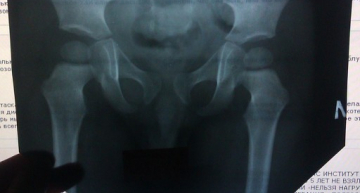

Добрый день! Уважаемые доктора, надеемся на помощь в нашем вопросе. В месяц ортопед, осматрев нашего малыша, сказал делать широкое пеленание и массаж ножек, т.к. разведение было не очень хорошее. В 2,5 месяца нам сделали УЗИ. Результат был таков: для возраста 2,5мес. показатели нормальные. Т.е. никаких проблем. Теперь нам 5мес. Ортопед осмотрел и сказал что внешне все хорошо - ножки разводятся нормально, складочки ровные. НО! По результам РЕНГЕНА нам поставили двустороннюю дисплазию, т.к. на снимке не было впадин (или чашечек) , т.е они еще не сформировались. Врач назначил подушку Фрейка, через месяца 2 на прием. Сказал что же ы 1,5 месяца хрящиков в этом месте быть не должно. и что когда малыш начнет ходить - ножка может соскочить и нехорошие последствия. ПОДСКАЖИТЕ , ЖДАТЬ ФОРМИРОВАНИЯ ЭТИХ ЧАСТЕЙ ТС В ПОДУШКЕ ФРЕЙКА ИЛИ БЕЗ НЕЕ??? углы ортопед поставил 18 и 19гр. СПАСИБО ЗАРАНЕЕ!